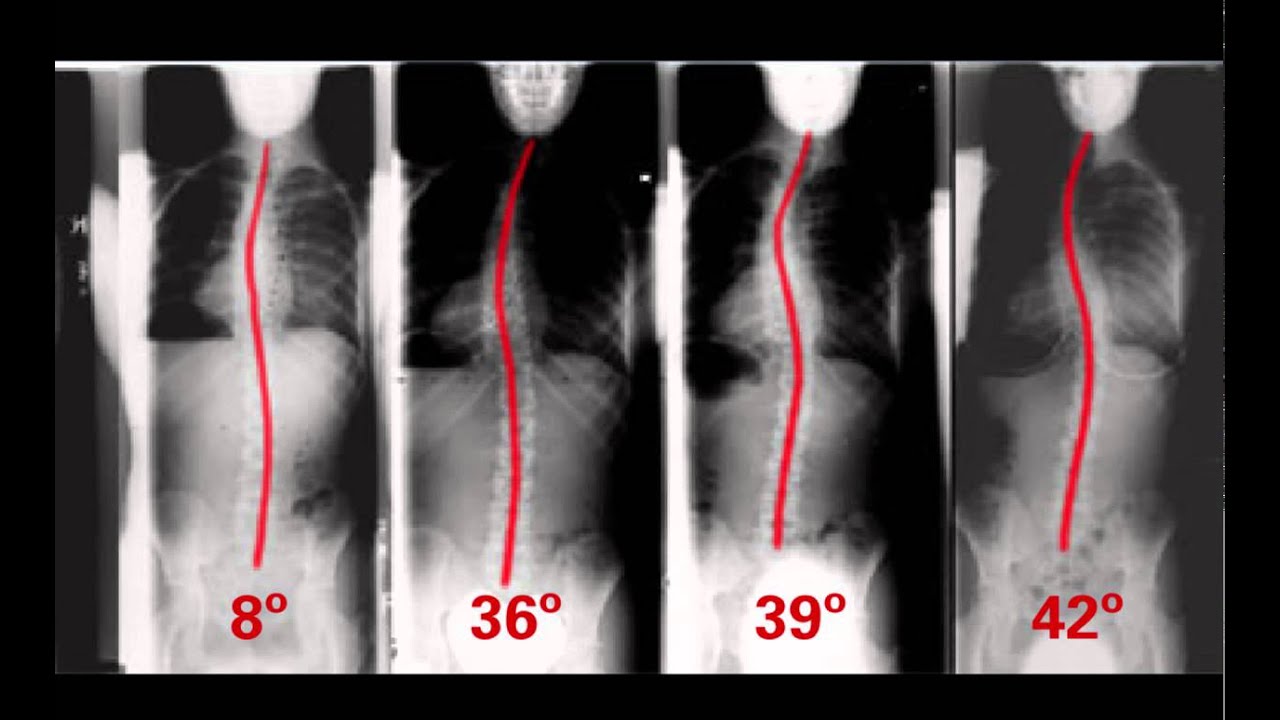

At 11years old, he has been diagnosed with a rare form of scoliosis.

His doctors have determined he will need to be immediately fitted for a brace that he will need to wear for 22 hours per day, (as an initial attempt to help correct his condition) with the possibility of additional treatment or surgery, due to the positioning of the syrinx in his spine and location of the curve.